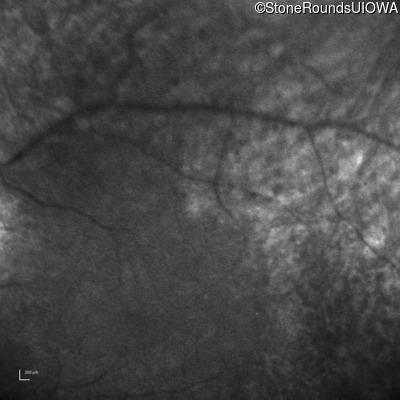

Infrared Fundus Photograph - Right -

No Light Perception

Exemplar

Infrared Fundus Photograph - Left -